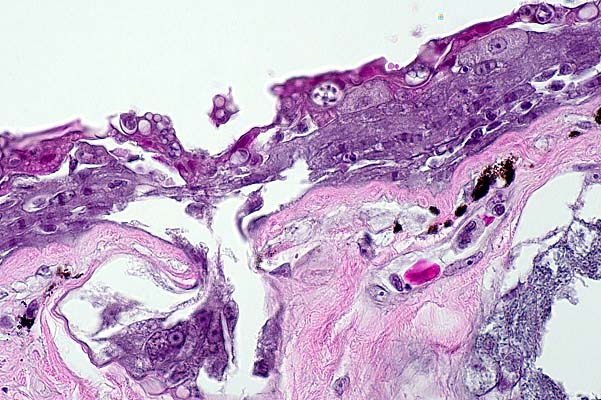

- Histologically, there is expansion of faveolar septa by edema

and variable infiltrates of predominantly heterophils with fewer

mononuclear inflammatory cells. Multifocally, within the lumen

there are aggregates of similar inflammatory cells admixed with

fewer sloughed epithelial cells, erythrocytes, rare bacteria

and cellular debris. Diffusely, there is marked hyperplasia and

hypertrophy of faveolar lining epithelial cells (type-2 pneumocytes)

with formation of syncytial cells that have 2-3, and occasionally

up to 10, nuclei. Occasionally, epithelial cells contain discrete

variably sized eosinophilic cytoplasmic inclusion bodies. Rarely,

within faveolar septa, there are trematode eggs, which are surrounded

by a thin rim of fibrous connective tissue and/or low numbers

of macrophages, which are often multinucleate. In addition to

virus isolation (noted above), transmission electron microscopy

of formalin-fixed lung tissue showed moderate numbers of filamentous

and spheroidal virions, morphologically suggestive of paramyxovirus,

budding from pneumocyte cell membranes.

- Case 29-2. Lung. Multifocally air sac epithelium contains

syncytial cells.

20x

obj

- Case 29-2. Lung. There are two deformed, collapsed,

empty, brown, trematode eggs expanding the interstitium.